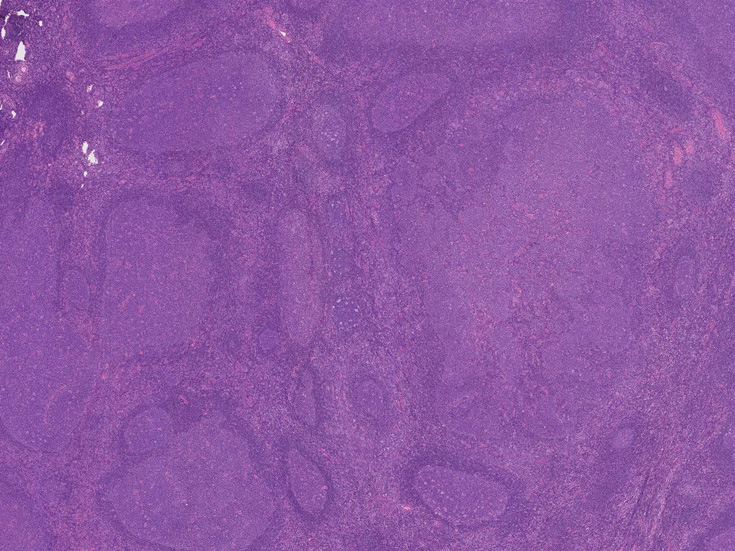

大きな胚中心を持つ多数のリンパ濾胞が見られる。胚中心の辺縁は不明瞭でマントル層も薄くなっている。1カ所マントル層リンパ球の侵入によりバラバラになった巨大な胚中心が認められ, macrofollicular patternと記載されるPTGCです。

鑑別にあがるfollicular lymphoma floral variantは全ての濾胞が腫瘍性であり, 本症例では除外可能と考える。

Diagnosis: Reactive lymphadenitis with PTGC